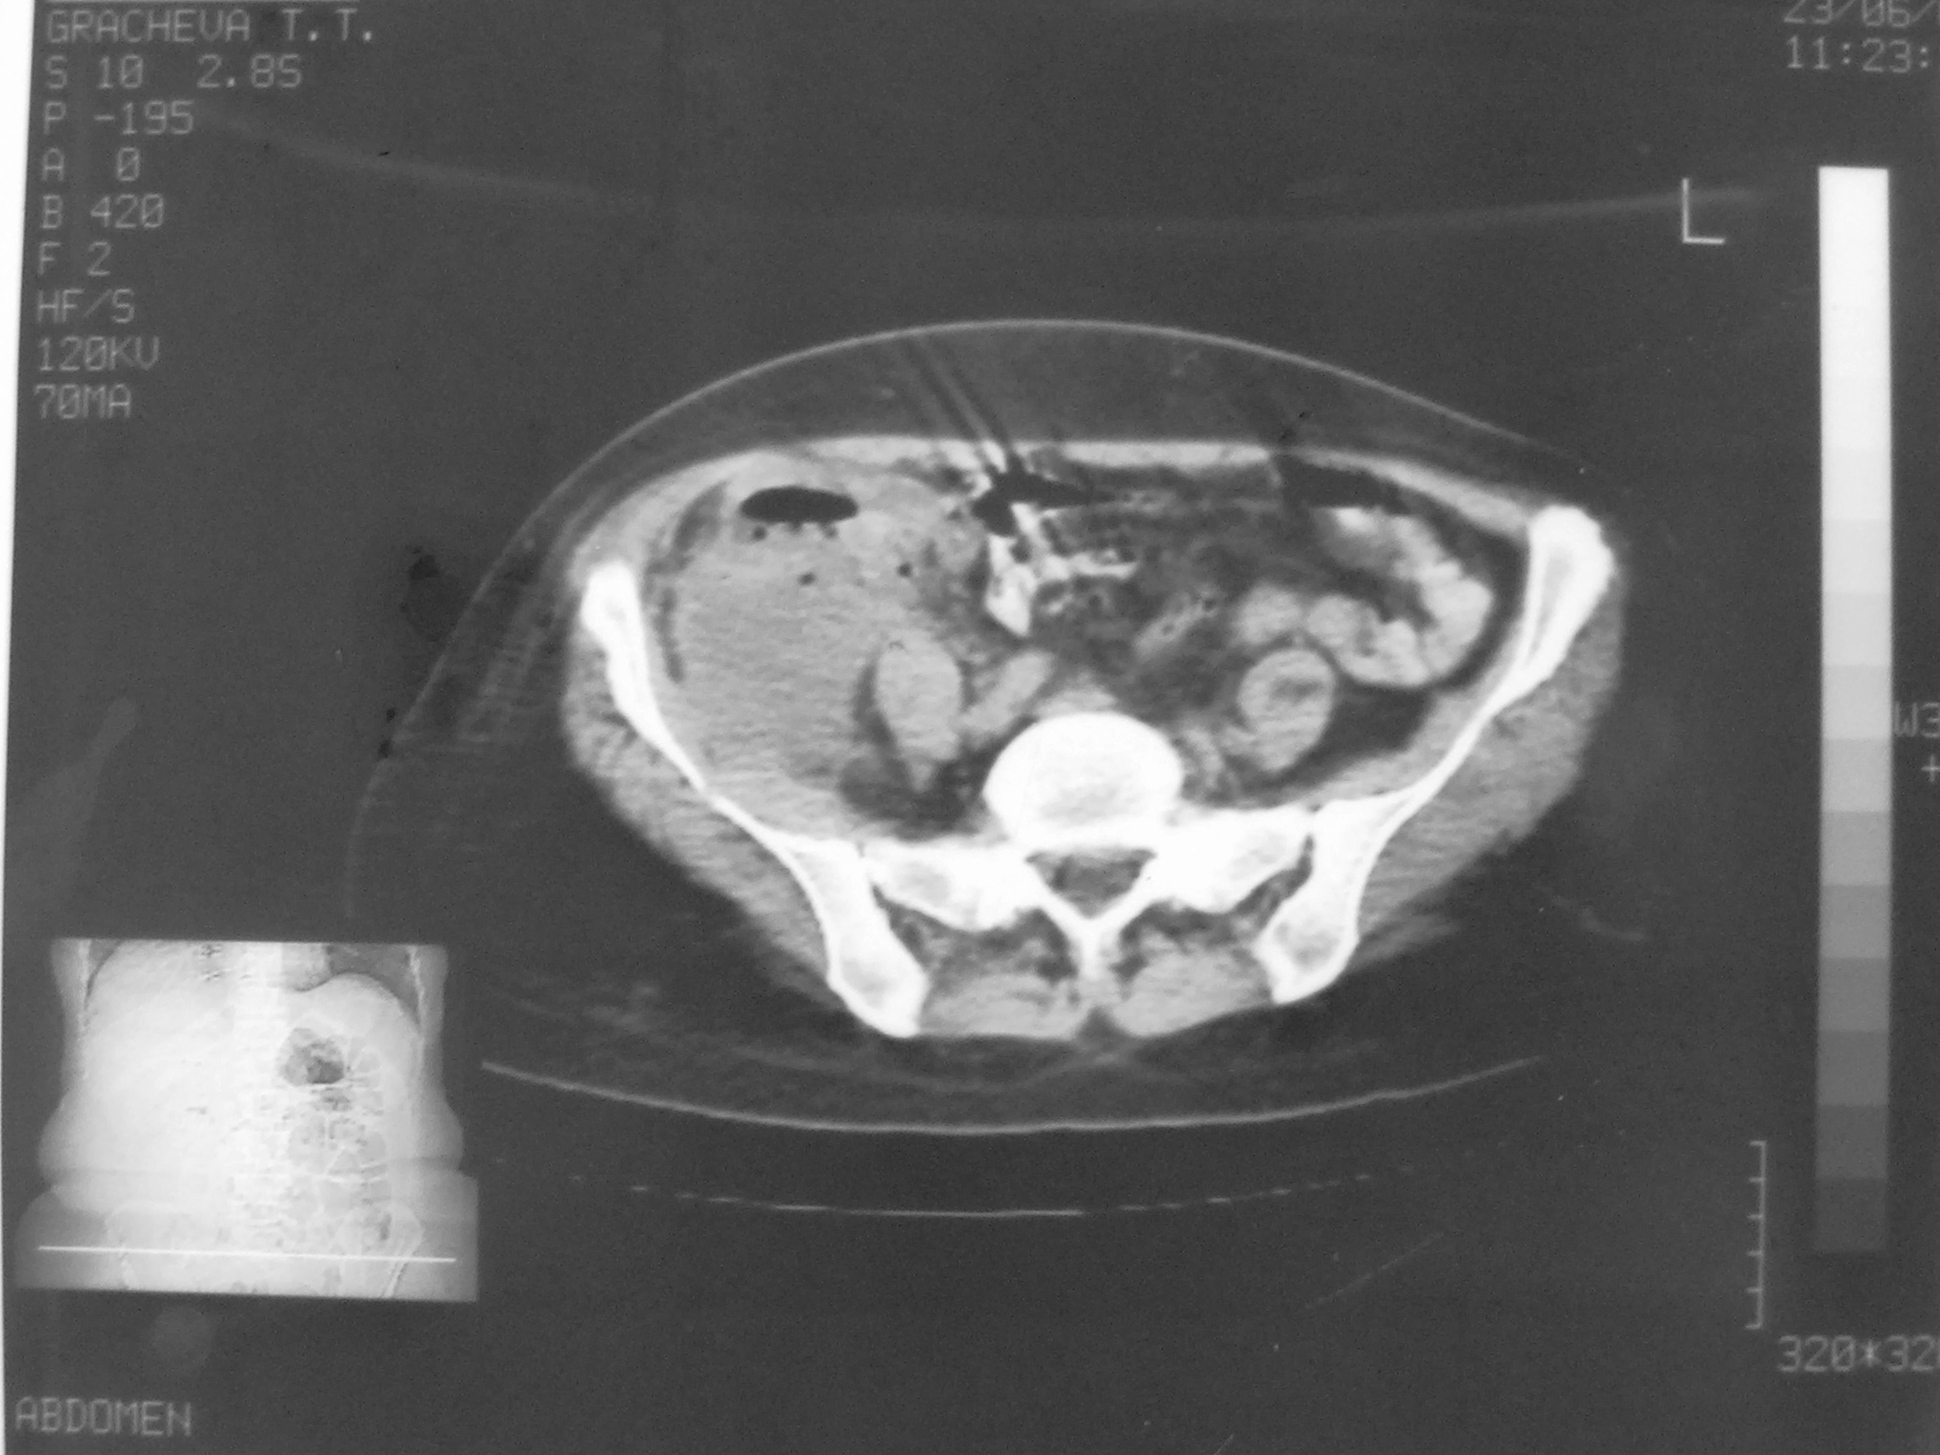

КТ диагностика тубоовариального абсцесса: Подходы и изображения

Раздел: Объективный взгляд